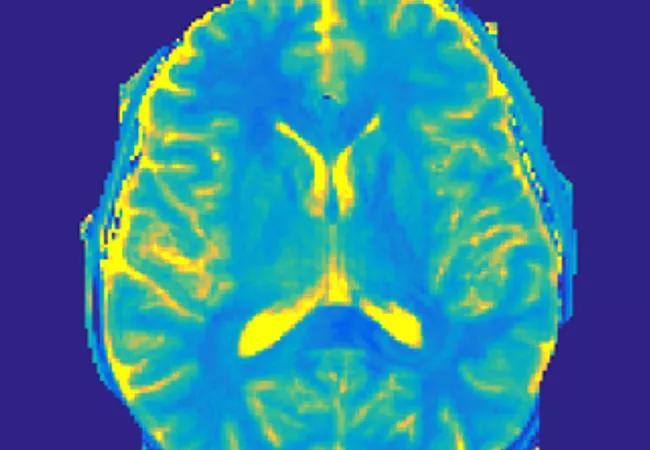

Essentials of MRF technology

MRF has emerged as an alternate imaging method that can successfully address problems associated with conventional and advanced imaging modalities.1 An example MRF image appears at the top of this post. This technology enables the noninvasive quantification of multiple properties of tissue simultaneously through a novel approach to data acquisition, post-processing and visualization.2 Instead of acquiring data by serial implementation of different sequences, MRF uses a randomized acquisition with varying values for image parameters:

Data acquisition is conducted with a highly undersampled variable density spiral k-space trajectory. The result of the acquisition is a set of time-resolved images in which the time course for each pixel reflects its underlying tissue properties. A dictionary is created by simulating the signal time courses that could appear in the data based on the pulse sequence used and ranges of T1 and T2 based on physiological limits. Each pixel is then matched to find the dictionary entry that most resembles its characteristics, resulting in a map of the tissue properties for each pixel. This pattern-recognition approach of data analysis makes MRF a robust quantitative imaging technique with high tolerance to motion or artifacts.